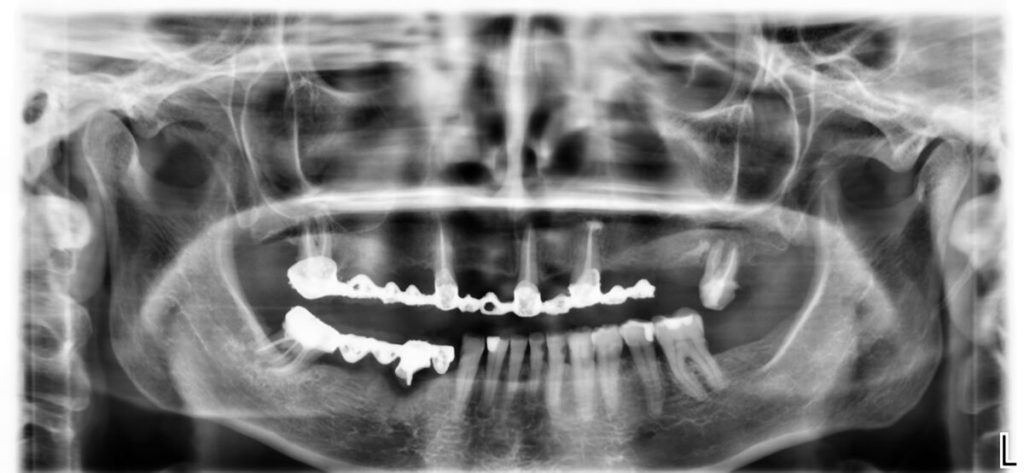

Technika All-on-X — I. fáze

- CBCT 3D, vyšetření, fotodokumentace